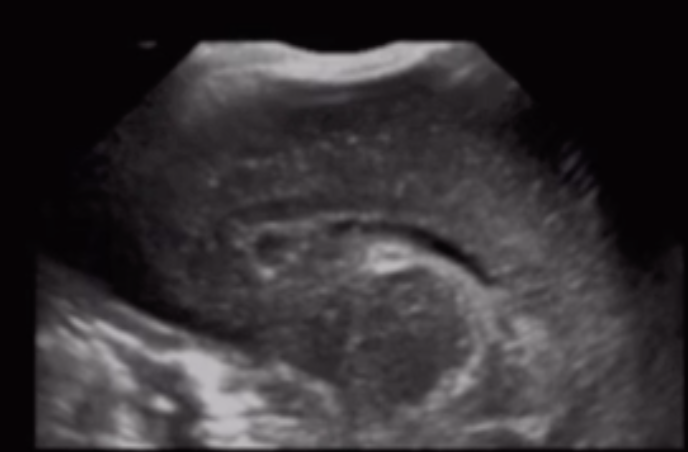

Germinal Matrix Hemorrhage

• The choroid plexus should not extend past the caudothalamic groove

• If you see bright stuff near there then suspect it is blood

• Only seen until 32-34W gestation

• You cannot have germinal matrix hemorrhage in a full term infant

• There is normally some increased echogenicity in the periventricular white matter

• So how do we know what is blood vs normal brain

• If prominently asymmetric = likely blood

• If area of increased echogenicity is as echogenic or more echogenic as the choroid plexus = likely blood

• Normal peri-ventricular brain should be echogenic but not more than the choroid plexus

• Can you identify borders of the echogenic area

• If yes = likely blood

• Normal brain will be more vague